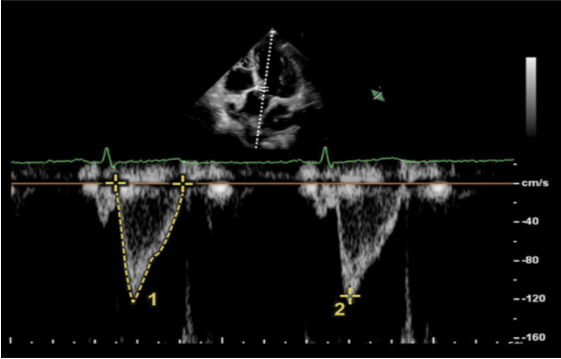

(3)下腔静脉塌陷度(cIVC):对自主呼吸患者而言,我们更多会采用IVC在患者主动呼吸时发生塌陷的程度(cIVC)来评价容量反应性,相关计算公式为:cIVC=(eIVC-iIVC)/eIVC×100%,eIVC代表下腔静脉呼气末直径,iIVC代表下腔静脉吸气末直径。一般来说,参考的cIVC>40%代表有容量反应性。根据美国超声心动图指南推荐,dIVC<2.1 cm伴用力吸气cIVC>50%时,考虑CVP为0~5 mmHg;dIVC>2.1 cm伴用力吸气cIVC<50%时,CVP相当于10~20 mmHg;当dIVC和cIVC不符合前面情况时,可以考虑CVP为5~10 mmHg。(4)颈内静脉(LJV)变异率:患者仰卧位床头抬高至30°,在颈内静脉短轴切面,使用高频线阵探头观察颈内静脉,然后旋转探头至长轴切面,通过观察颈静脉呼吸周期中的塌陷来评估。在机械通气患者,LJV扩张超过18%,或者LJV扩张超过7%合并PPV超过12%,可以定义为有容量反应性。(5)左室流出道速度-时间积分(VTI)或心排量(CO):在心尖五腔心切面,对主动脉-左室流出道采用PW模式,描记患者的血流频谱,可以获得每次搏动下速度-时间的积分(VTI)(图7),每搏量(SV)=VTI×π×(左室流出道直径/2)2,心排量CO=SV×HR。在进行被动抬腿试验(PLR)的患者中,若PLR前后,VTI或SV或CO增加比例超过12%,患者排除使用弹力袜、严重低血容量、腹肌紧张、腹腔高压后,则证明患者存在容量反应性。